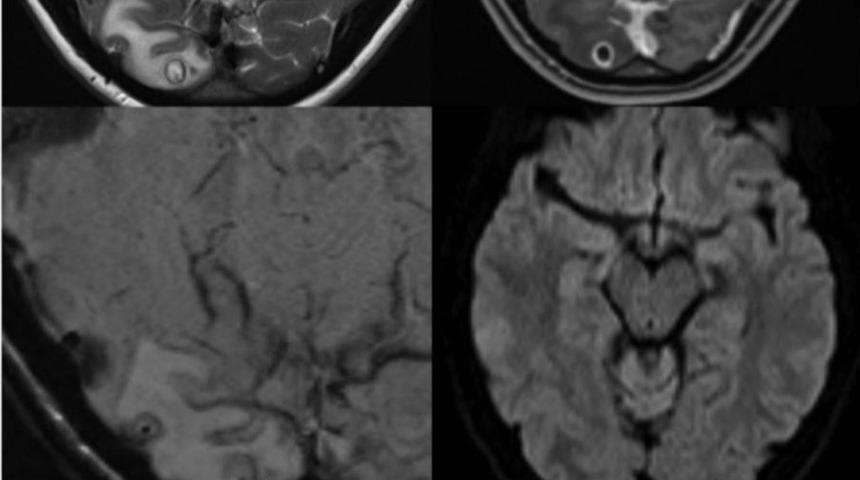

Doktorların yaptığı MR taramasının ardından kadının başının arkasındaki oksipital lobda 8 mm uzunluğunda bir lezyon bulundu.

Cerrahlar, herhangi bir komplikasyon yaşanmadan kiste benzeyen şeyi çıkarmayı başardı; ne var ki çıkardıkları parçanın insan dokusu olmadığını gördü.

DNA testi, insanlara genelde az pişmiş domuz etinin yenmesiyle bulaştığı için domuz tenyası olarak da bilinen Taenia Solium'la bir eşleşme buldu.